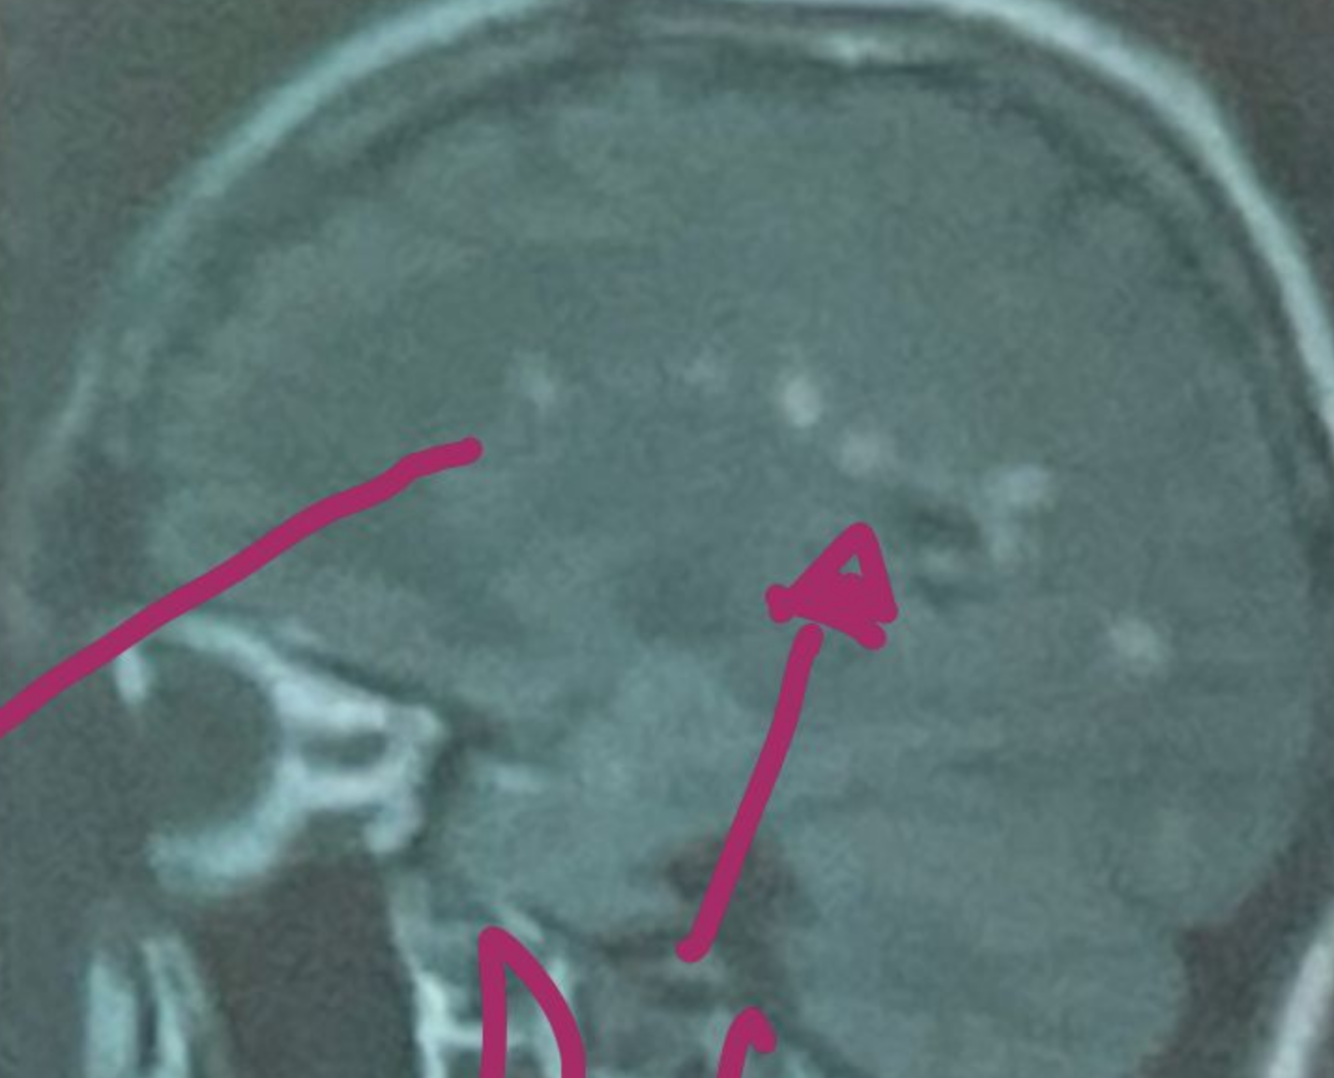

En la resonancia magnetica la esclerosis multiple da estos signos:

Hiperintensidad en T2 y FLAIR

Hipointensidad en T1

Lesiones redondas y ovaladas, bordes definidos menores a 5mm

RM de encefalo positiva